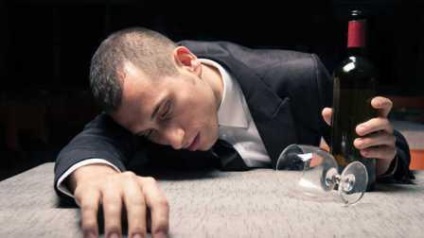

Alkoholos dementia, a tünetek és a kezelés

A demencia súlyos betegség a központi idegrendszer, ami a visszafordíthatatlan memória elvesztése. Demencia a háttérben alkoholizmus végződik a teljes változás az egyén személyisége és intelligenciája.

Mi demencia alkoholizmus?

Hogy van az alkoholos dementia?